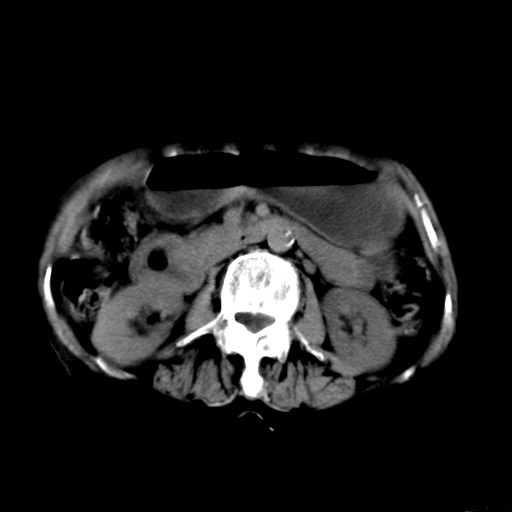

以下是引用杀毒软件在2009-3-4 17:38:00的发言:[br]为何没有喝照影剂呀? 胆总管及肝内胆管扩张,增强吧。[br][br]考虑-----十二指肠占位----建议----十二指肠镜检查[br][br]

以下是引用jiangjing在2009-3-4 17:45:00的发言:[br]低位胆道梗阻。十二指肠降段局部管壁增厚。扫描效果不理想,建议ct增强及ercp。

以下是引用杀毒软件在2009-3-4 17:38:00的发言:[br]为何没有喝照影剂呀? 胆总管及肝内胆管扩张,。增强吧。[br][br]考虑-----十二指肠占位----建议----十二指肠镜检查[br][br][br][br][本贴已被 杀毒软件 于 2009-3-4 17:56:38 修改过]